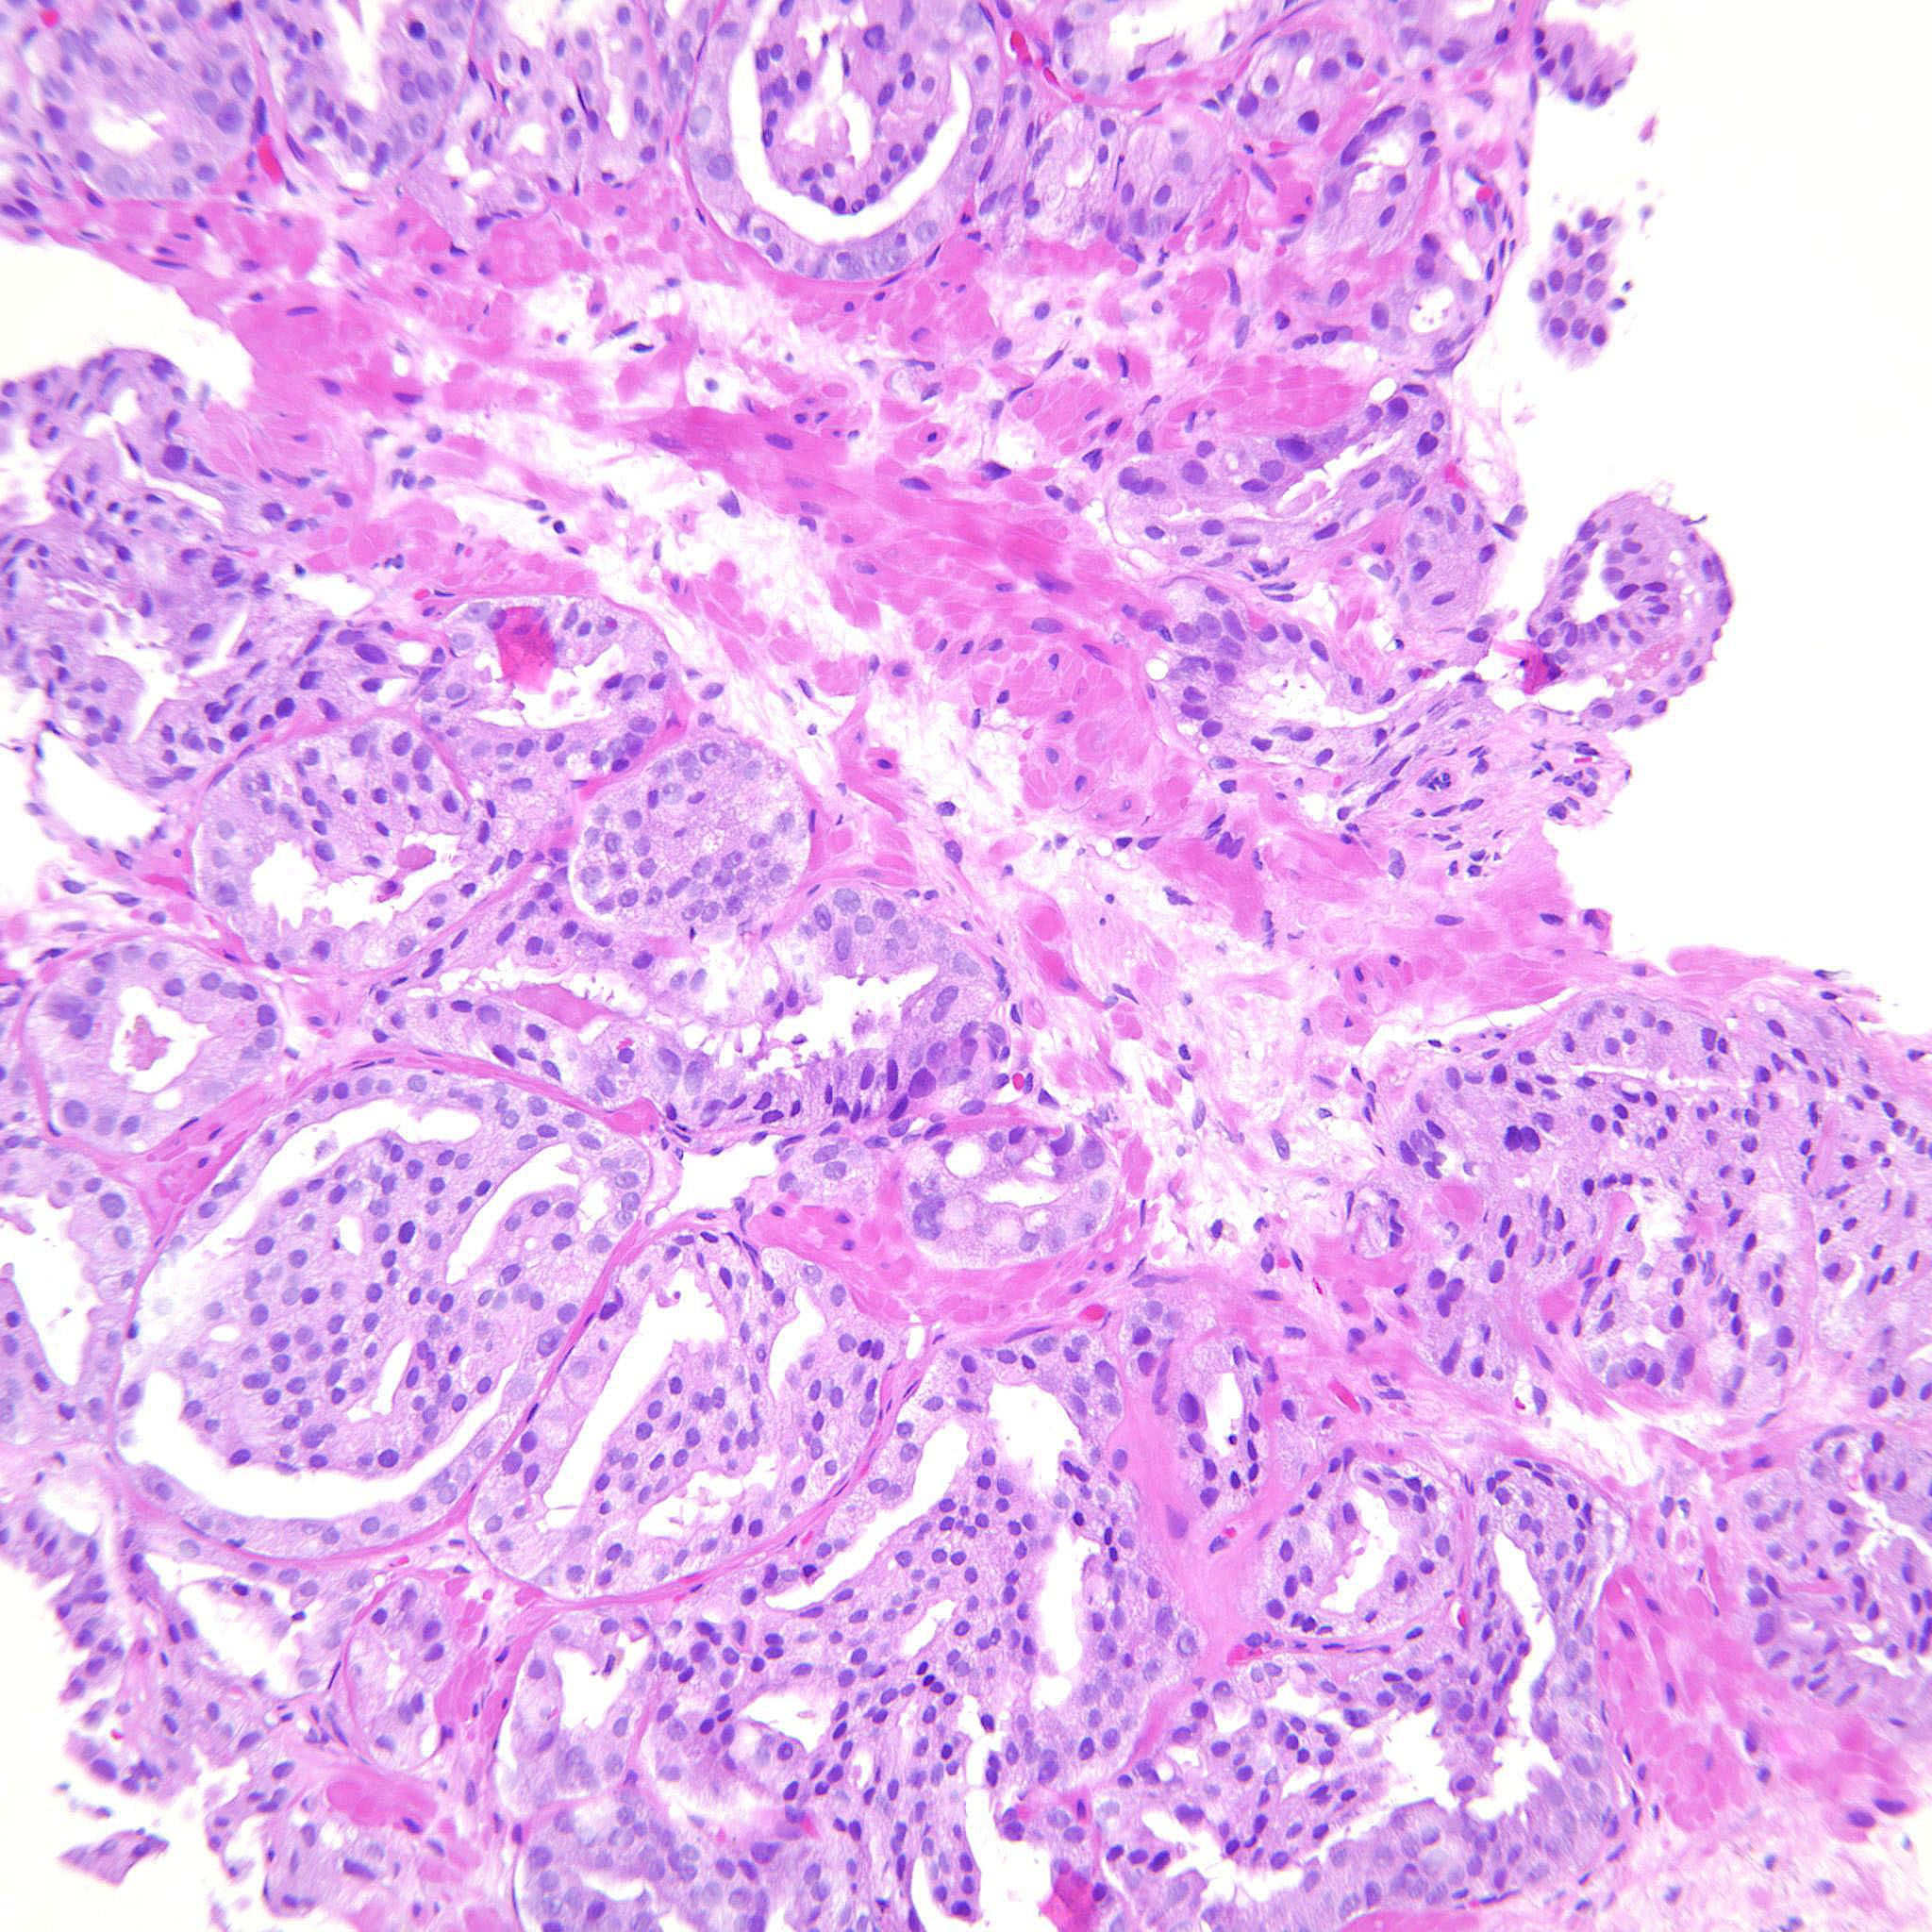

Case description (by case creator):

Gleason pattern 4 with glomeruloid bodies. There is also a GP 3 component.